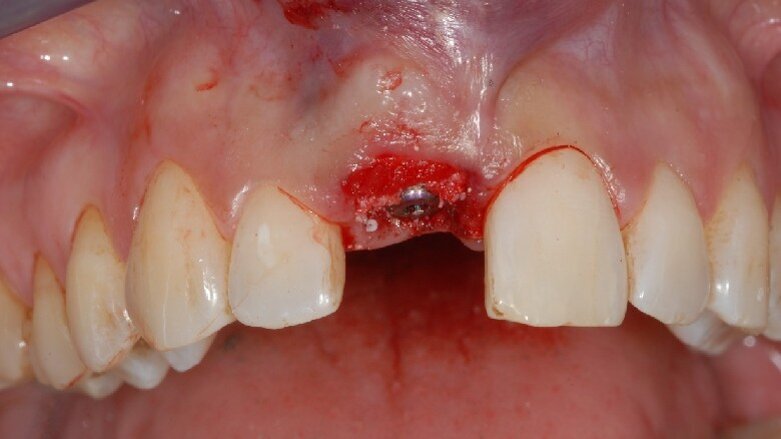

Il primo passo prevedeva l’estrazione dell’incisivo dapprima mediante l’uso di un sindesmotomo e poi per mezzo di una pinza facendo attenzione a preservare il più possibile il sito anatomico e non rompere le pareti alveolari. Dopo l’estrazione, l’osso alveolare è stato esplorato con una sonda parodontale, per valutarne l’integrità e per determinare quale diametro di impianto utilizzare.

L’impianto è stato inserito 3 mm apicalmente al margine gengivale libero (Nobel Active, Nobel Biocare), al centro dell’alveolo, leggermente posizionato verso il lato linguale con un corretto posizionamento 3D14. Sembra logico inserire un impianto di lunghezza e diametro sufficiente per un ancoraggio ottimale.

Immediatamente dopo aver ribasato una corona provvisoria, lo spazio tra l’impianto e le pareti ossee è stato riempito con del sostitutivo osseo equino (Calcitos, Bioactiva, Ita) per prevenire un possibile riassorbimento con conseguente danno estetico. Il biomateriale è stato inserito fino al livello del margine gengivale libero, per riempire senza eccessiva pressione tutto lo spazio tra la corona, l’impianto e l’osso alveolare15.

Infine, visto che la forma, lo spessore e la quota di gengiva cheratinizzata erano ideali, i tessuti sono stati elevati a tunnel attraverso la parabola senza nessuna incisione di rilascio ed è stata inserita una matrice dermica (Creos Mucogain, Nobel Biocare, Swiss) per migliorare e mantenere il tono dei tessuti stessi al posto di un più classico innesto di tessuto autologo connettivale (Fig. 3).

Fig. 3 - Appena inserito l’impianto il gap tra impianto e osso alveolare è stato zeppato con del biomateriale e tra i tessuti molli e il piatto osseo buccale è stata inserita una matrice dermica.